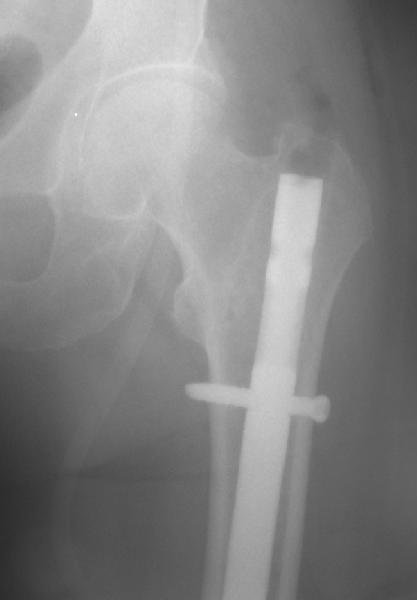

То, что планируется - наиболее распространенный подход. Еще менее инвазивный вариант - закрытый антеградный интрамедуллярный остесинтез. Мы используем гвозди, которые выпускаются предприятием ЦИТО, т.е. недорогие. Там в дистальное отверстие можно ввести 3 винта (2 снаружи и один навстречу), еще и угловая стабильность получается.